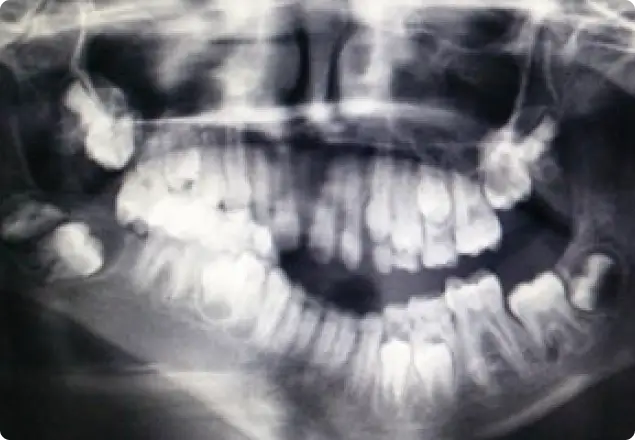

Panoramic radiograph reveals mixed dentition phase with multiple developing tooth buds. Zygomatic process cannot be traced completely on the right side. The right half of the mandible from the symphysis region appears sharply bent upto the angle region. Right side temporo-mandibular joint is not appreciable,